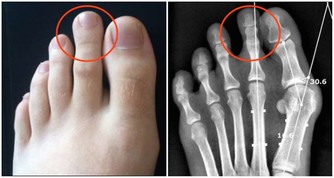

人體的上段腰椎位置相對較高,當此處出現椎間盤突出或骨刺時,可能會壓迫附近的神經根,造成相關部位放射痛。其中,第四腰椎是最容易受損的一節。

由第四腰椎神經根所支配的正是髂骨後區域,這也稱為括約肌皮區域。當神經根受到壓迫,就會產生胯後部及大腿外側放射痛,這就是間盤突出引起的典型「坐骨神經痛」。

而第三、五腰椎的病變,也可能觸發胯部放射痛。因為它們的神經根分別與皮支神經、股神經有關。這些都是支配下肢感覺的重要神經。